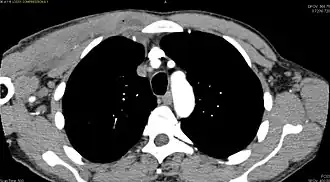

| Transverse T2 magnetic resonance imaging section through the hip region showing abscess collection in a patient with pyomyositis. | |

| Diagnostic method | Diagnostic method used for PM includes ultrasound, CT scan and MRI. Ultrasound can be helpful in showing muscular heterogeneity or a purulent collection but it is not useful during the first stage of the disease. CT scan can confirm the diagnosis before abscesses occur with enlargement of the involved muscles and hypodensity when abscess is present, terogenous attenuation and fluid collection with rim enhancement can be found. MRI is useful to assess PM and determine its localization and extension |